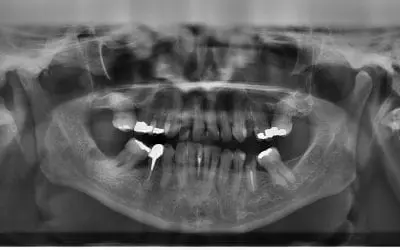

The Challenges of Wisdom Teeth

Anthropologists believe that wisdom teeth, our third set of molars, were needed by our ancestors to chew through their diet of rough, coarse food. Wisdom teeth have no function in processing today’s softer foods. For...